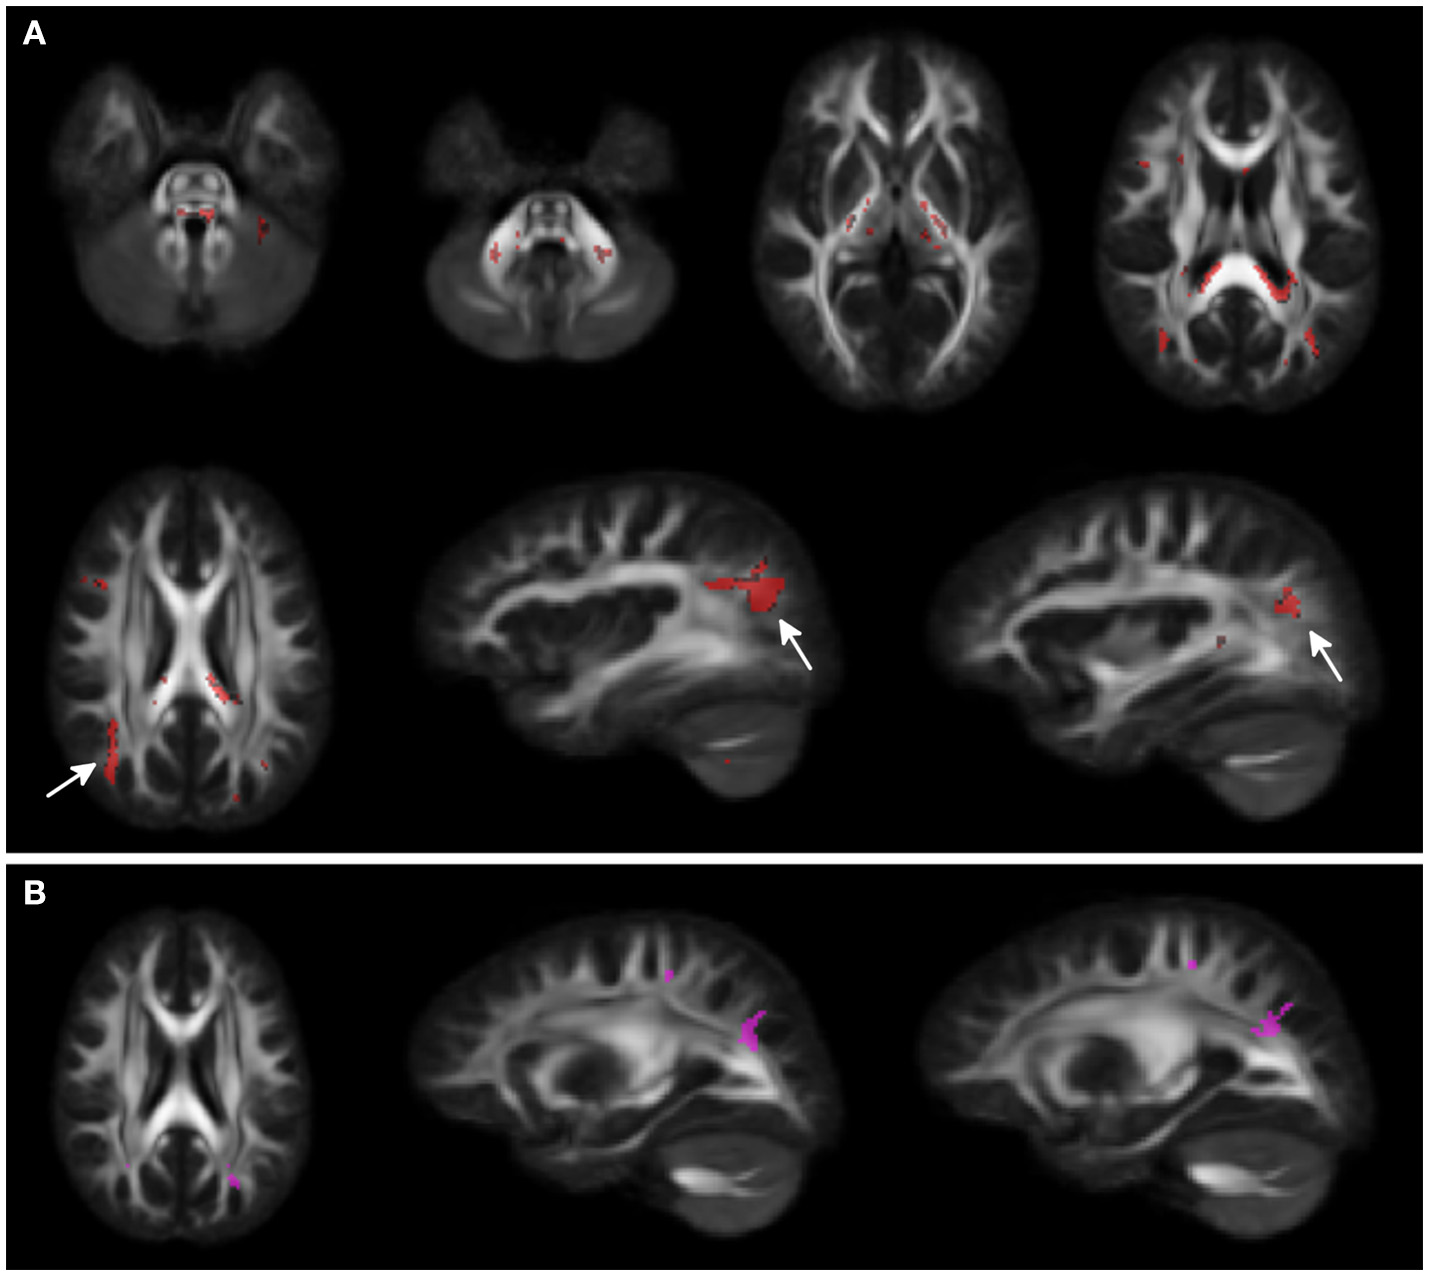

Voxel-wise analysis showed clusters of lower FA in middle and superior cerebellar peduncles, posterior limbs of internal capsules, and in the splenium of corpus callosum for WS patients compared to HCs. A larger cluster of lower FA was observed in the subcortical white matter of the parieto-occipital region bilaterally. A small cluster of higher FA was present in the adjacent parieto-occipital white matter of the left hemisphere, in WS patients compared to HCs (Figure 1).

Figure 1

Voxel-wise Fractional anisotropy (FA) differences between Williams Syndrome (WS) and healthy controls (HC). Panel (A) (First 2 rows) shows in red the areas where FA values are lower in WS patients compared to the HCs. Arrows point at bilateral parieto-occipital clusters. Panel (B) shows the small cluster of higher FA in the left hemisphere (arrowheads) for the WS group compared to the HCs. Significance level is set at p < 0.05 corrected for multiple comparisons.

DTI analysis revealed areas of lower FA both in deep (cerebellum, posterior limbs of internal capsules, in the splenium of corpus callosum) and subcortical regions (WM of the parieto-occipital region bilaterally) for WS patients compared to HC. Congruent with the peculiar cognitive profile, where the visual spatial impairment is prominent, we also found an asymmetrical involvement of parieto-occipital regions, with lower FA in the right hemisphere of the WS patient group. Previous literature has reported both higher and lower FA. Higher FA was observed in superior and inferior longitudinal fascicles, whereas lower FA values were reported in the posterior limbs of the internal capsules, middle and superior cerebellar peduncles, splenium of the corpus callosum, subcortical WM of the parieto-occipital regions bilaterally and in the uncinate fasciculus, which have been linked to the language, motor, visual spatial and face processing competences (37–39).